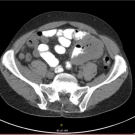

A 66-year-old man presented to the emergency department (ED) with mid and left upper quadrant abdominal pain and shortness of breath. The patient had been complaining of coughing and increased shortness of...

In this Consultant Case Report Insights, Nandini N. Patel, OMS III, speak about her study, “Metastatic Malignant Melanoma from Unknown Origin to the Jejunum: A Case Report.” Nandini Patel discusses the...